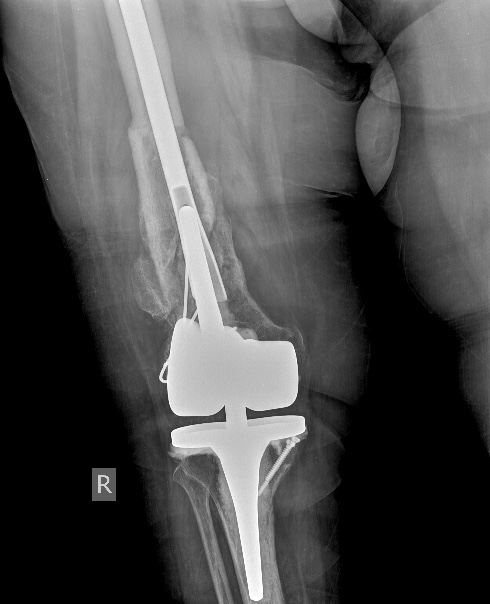

[Ortho] Перипротезный перелом бедра у ребёнка

Оптимальное решение - закрытый остеосинтез интерамедуллярным стержнем с

удлинением ножки эндопротеза. Пример в приложении. Делает такие стержни

предприятие ЦИТО.

Имя     : 1.jpg